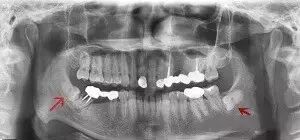

在X线片上可以看得很清晰。